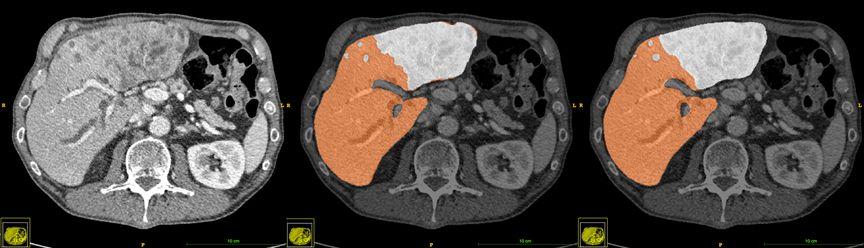

图1-8是肝脏及结节分割技术的影像分析结果。

▲图1-8 肝脏及结节分割技术,从左至右:CT原始影像、真实结果、算法结果